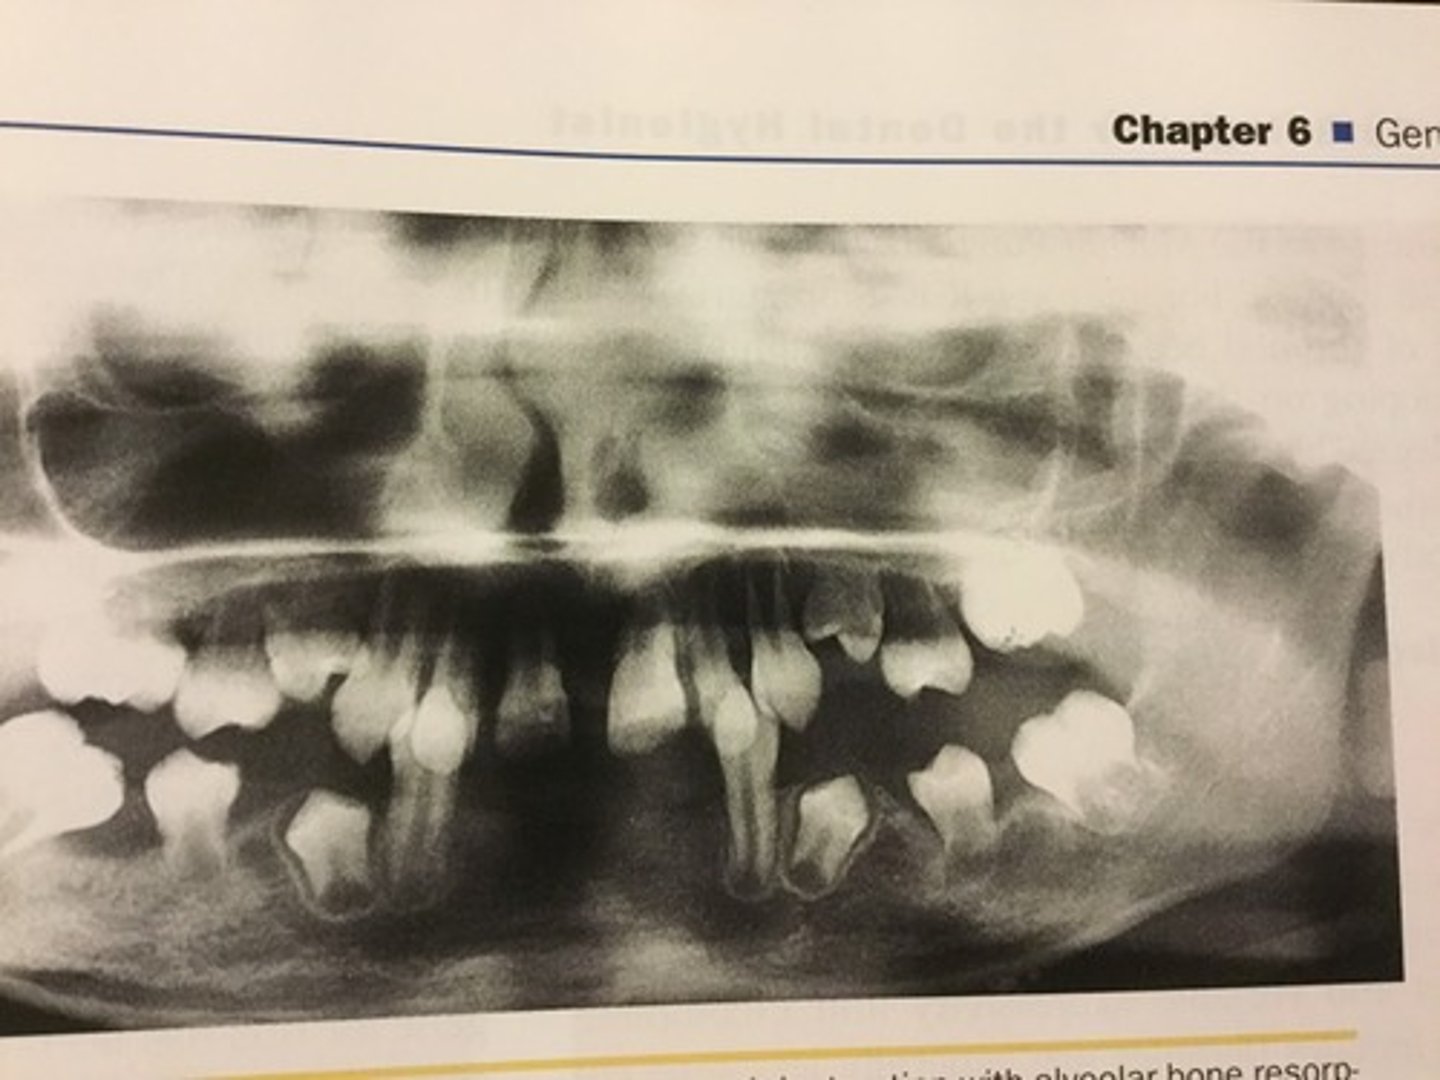

Gingival and periodontal disease has been reported in _______ of affected individuals with down syndrome

90%